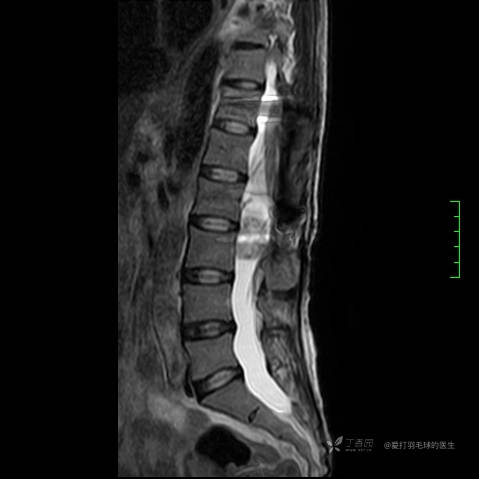

主诉:患者因反复右侧腰痛伴右下肢麻木2年余入院。

简要病史:自诉右甲状腺功能亢进症多年,规律服药,平素多有心悸、胸闷、活动后明显。既往腰椎椎管内肿瘤切除术。